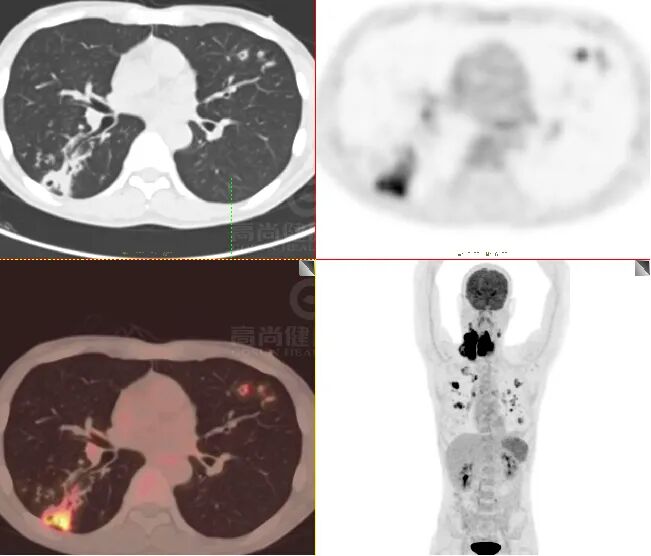

PET/CT 图像

痰培养提示

产酸克雷伯菌感染